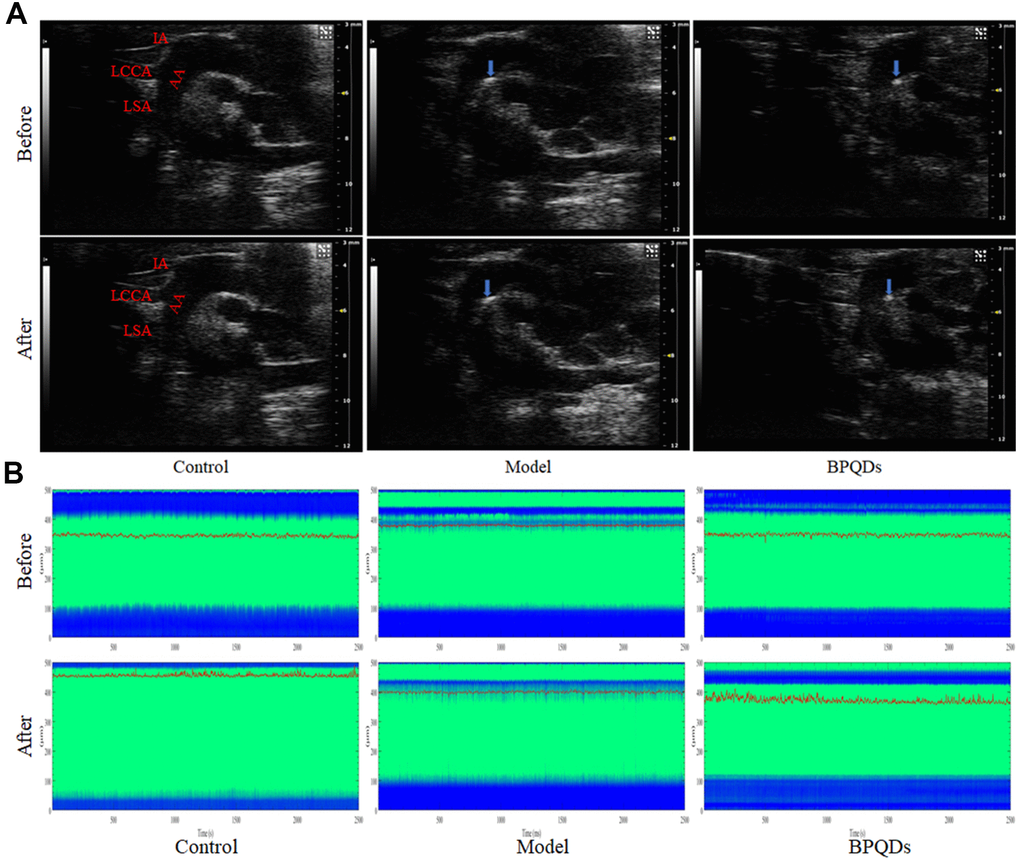

Ultrasonography

Ultrasonography showed that atherosclerotic plaques appeared in the aortic arch of Apoe−/− mice fed a high-fat diet for 12 weeks (including the model group and BPQD group), demonstrating successful establishment of the atherosclerotic mouse model. After 3 weeks of treatment, the plaques in the aortic arch of the model group continued to grow, while that in the BPQD group decreased (Figure 7A). The innominate artery elasticity of the BPQD group was higher than that of the model group, and the peak systolic velocity (PSV) of the innominate artery in the BPQD group was higher than that in the model group (Supplementary Figure 8A, 8B).

Photoacoustic microscope

Photoacoustic microscopy showed that the abdominal aortic vascular elasticity in the BPQD group was higher than that in the model group, and the response of the abdominal aorta to the vasodilator quinidine in the BPQD group was higher than that in the model group (Figure 7B and Supplementary Figure 8C).